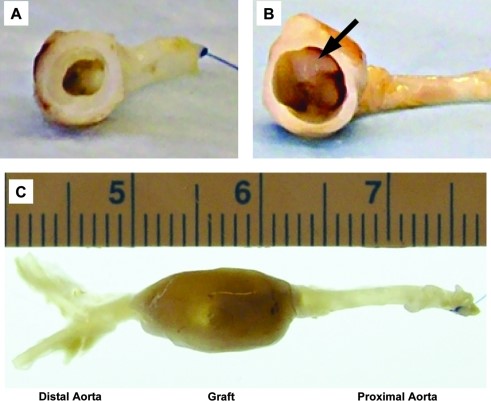

Tuy nhiên, việc sử dụng trực tiếp các mạch khử tế bào để ghép vẫn còn nhiều thách thức liên quan đến hiện tượng phình động mạch, rối loạn huyết động và tắc nghẽn mạch máu, dẫn đến tỷ lệ sống sót của vật chủ thấp. Trong nghiên cứu của Gui và các cộng sự, các mạch dây rốn khử tế bào trước ghép có đường kính trong là 1,5 mm (tại áp lực zero), khá tương đồng với kích thước động mạch chuột cống (khoảng 1 mm). Tuy nhiên, đường kính mạch tăng lên nhanh chóng và đạt xấp xỉ 4,5 mm sau khi ghép (Hình 5).

Do đường kính không khớp, kiểm tra siêu âm động mạch chủ cho thấy dòng chảy bị rối loạn gần vùng nối và lưu lượng dòng chảy trong mạch ghép thấp hơn đáng kể so với động mạch của vật chủ. Tỷ lệ huyết khối cấp tính ở những mạch ghép khử tế bào có lẽ là do thiếu lớp nội mạc và sự tiếp xúc của collagen trên bề mặt mạch với dòng máu chảy không được chống đông. Sự giãn thành mạch cũng có thể xảy ra bởi sự suy yếu trong cấu trúc thành mạch do thiếu sự hiện diện của tế bào. Những vấn đề trên cho thấy, để mạch máu dây rốn có thể được sử dụng như nguồn ghép các mạch máu nhỏ, vẫn cần phải có những nghiên cứu để giải quyết được những nhược điểm của động mạch khử tế bào.